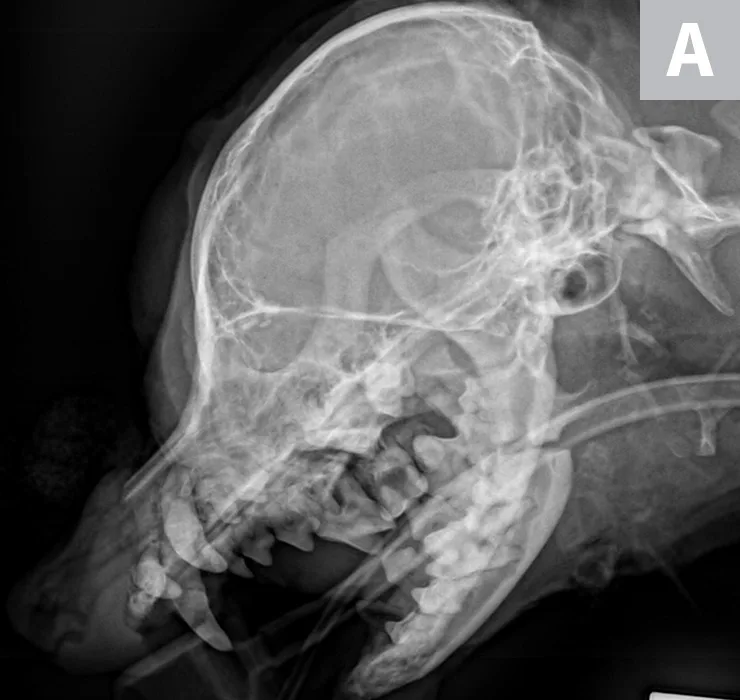

FIGURE 3A

Lateral radiographs of a caudal mandibular body fracture (A) and placement of 2 interfragmentary wires (B) in a dog